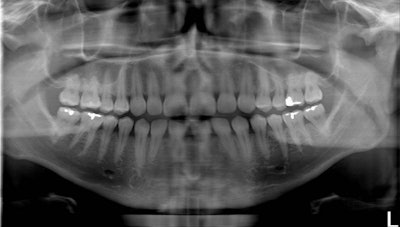

Standard panoramic image from a PC-1000 system using a CdTe sensor from Ajat, self-corrected with tomosynthesis software. Images courtesy of Dr. Robert Langlais.

Although the front teeth are distorted, the back teeth are no longer crossed. By manually positioning the patient in the system, the contacts are now open.